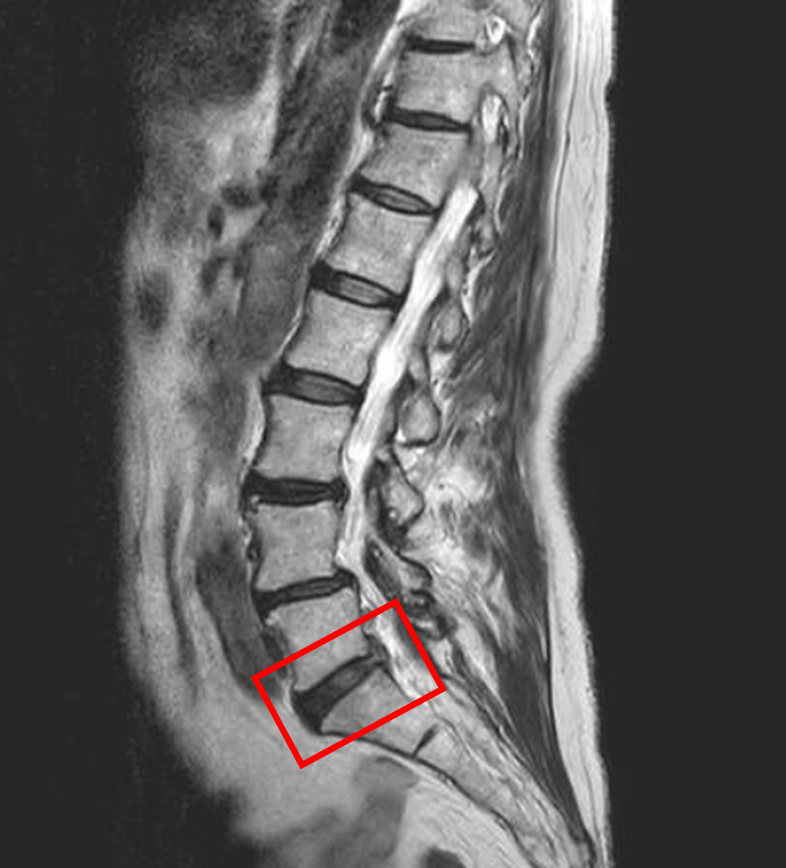

この患者様は赤い枠で示されている箇所(L5/s)に椎間板ヘルニアを認めます。

L3/4,4/5も椎間板変性を認めます。